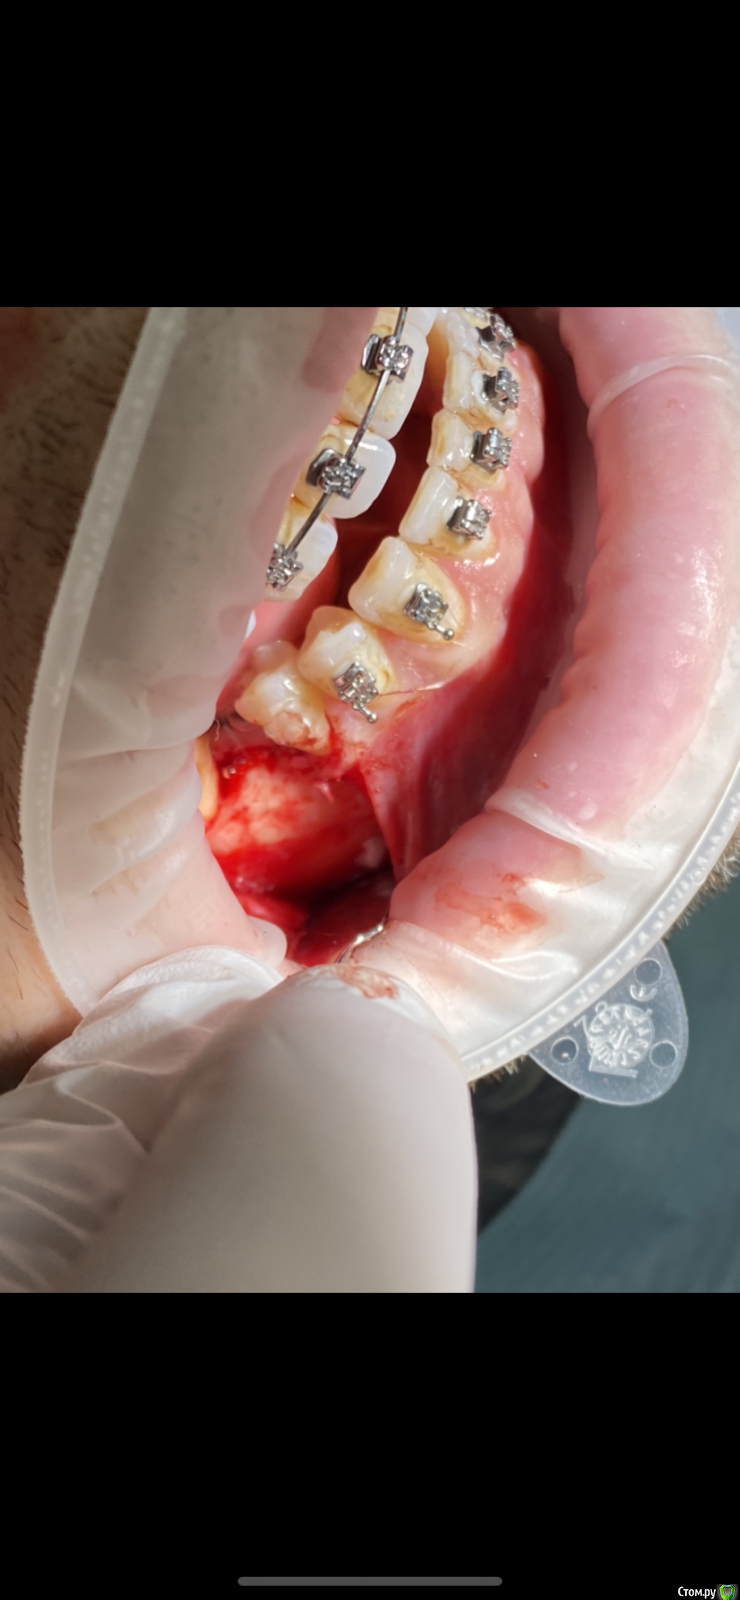

It'sGeorgy Опубликовано 7 февраля, 2020 Автор Поделиться Опубликовано 7 февраля, 2020 (изменено) Заколхозил лоскут => налепил житкотекучего на кость(стрелкой на снимке), чтобы понять там ли планирую пилить, сделал оптг => выпилил => вытащил => через месяц пластика мягких тканей + имплантат. А ментальное отверстие в 2 мм от окна отлично держало меня в тонусе на протяжении все операции. Изменено 7 февраля, 2020 пользователем It'sGeorgy 1 Ссылка на комментарий

Spon Опубликовано 8 февраля, 2020 Поделиться Опубликовано 8 февраля, 2020 Заколхозил лоскут => налепил житкотекучего на кость(стрелкой на снимке), чтобы понять там ли планирую пилить, сделал оптг => выпилил => вытащил => через месяц пластика мягких тканей + имплантат. А ментальное отверстие в 2 мм от окна отлично держало меня в тонусе на протяжении все операции.Все правильноПытаться удалить образование через 4 мм отверстие это заведомо провальная тактика,не получилось бы,маленькое окноКиста рецидивирует если оставить хоть немного оболочки,надо вычищать полностью до гладкой кости Ссылка на комментарий